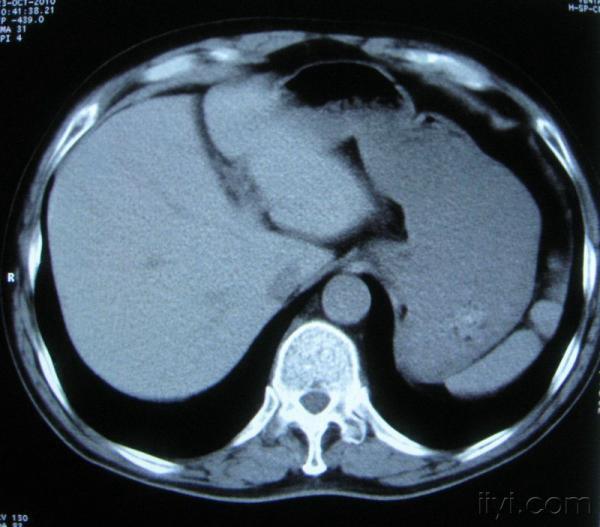

男。60岁,胸片示支气管炎治疗后复查CT。

你指那个肯定是淋巴结,中央系坏死,这很常见,特别在双侧腹股沟会经常看到。这个双侧腋窝及纵隔见多发小淋巴结征。

根据位置考虑应该是淋巴结,密度不均,是因为肿大的淋巴结中心液化坏死